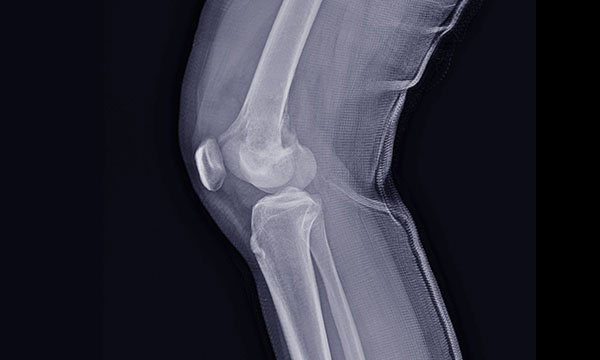

To explore the distinguishing features of benign and malignant bone tumours on X-ray

Bone tumours can present a diagnostic challenge for healthcare professionals working in the emergency department (ED). They are often asymptomatic and therefore not detected until an injury, such as a fall or trauma, prompts the patient to present to the ED. Nurses working in the ED are likely to encounter patients with a bone tumour in the course of their professional life, so they need to have the knowledge and skills to adequately assess, manage and refer these patients. This article provides an overview of benign and malignant primary bone tumours, describes the assessment of their signs and symptoms, and explains the distinguishing features of benign and malignant bone tumours on X-ray. It also details the case of a patient who presented to the ED with a traumatic knee injury and was diagnosed with a benign bone tumour.